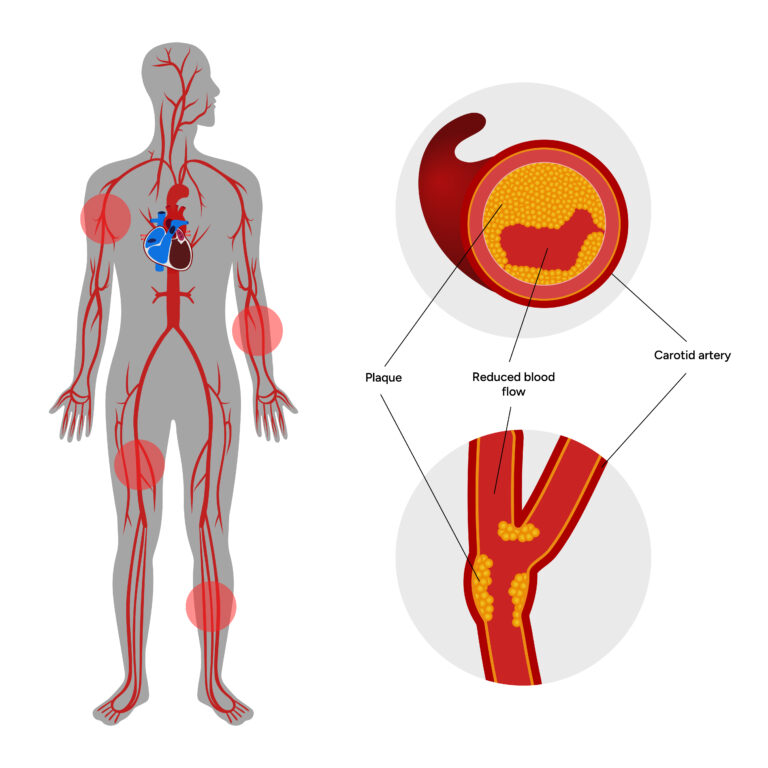

Peripheral Artery Disease (PAD) is a serious condition where the arteries supplying blood to the legs and feet become narrowed or blocked due to plaque buildup (atherosclerosis). This results in reduced blood flow, causing leg pain, difficulty in walking, non-healing ulcers, and in severe cases, risk of amputation.

Causes of Peripheral Artery Disease

- Atherosclerosis (cholesterol/plaque deposits in arteries)

- Diabetes mellitus

- High blood pressure (hypertension)

- High cholesterol

- Smoking

- Obesity and sedentary lifestyle

- Family history of vascular disease

- Early diagnosis is crucial. If left untreated, PAD can progress to critical limb ischemia, requiring urgent treatment to prevent amputation.